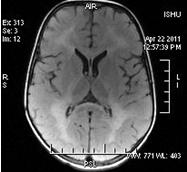

A 3-year-old male was presented with complaints of delayed milestones, language impairment, gradually increasing spasticity, difficulty in swallowing, and abnormal movements. Patient was a product of non-consanguineous marriage, born by normal vaginal delivery with no significant antenatal, intranatal, and immediate postnatal events. Patient was the youngest of eight siblings, of which six female siblings were healthy, normal, and growing appropriately for age, but one male sibling died of similar complaints at around 5 years of age. Parents noticed some abnormal jerky movements of eyes starting from second month of life. His milestones were delayed and he was not able to support his head by the age 6 months and he never achieved sitting or standing without support but he was able to sit with support. He also had stridor, difficulty in swallowing, language impairment, and tonic-clonic convulsions and he was being managed with a diagnosis of cerebral palsy and was referred to our centre for further management. On detailed physical and neurological examination, patient was having pendular nystagmus, stridor, spastic quadriparesis, hyper-reflexia, and positive Babinski sign. Palatal and gag reflexes were weak with some difficulty in swallowing and global developmental delay. During hospital stay, he had 2 episodes of tonic-clonic convulsions which subsided with antiepileptics. His routine haematological investigations and chest X-ray were within normal limits. Auditory and visual evoked potentials were normal. MRI brain imaging revealed diffuse and symmetric T2 and flair high signal intensity throughout the bilateral cerebral white matter, genu of corpus callosum and subcortical U fibres along with tigroid pattern within the corona radiate (Figures 1-2). On the basis of these clinical and imaging findings diagnosis of Pelizaeus-Merzbacher disease (PMD) was made and treatment with antiepileptics, antispastic medications, and physiotherapy was started to reduce spasticity and convulsions.

Fig.1 - T2-weighted image showing diffuse hyperintensity throughout cerebral white matter.

Fig.2 - Flair image showing hyperintensity involving bilateral cerebral white matter, corpus callosum, and subcortical U fibres.

Classic PMD usually presents with infantile-onset nystagmus, weakness, developmental delay followed by development of ataxia, spasticity, involuntary movements, and cognitive delay. Most patients never ambulate, although some language skills may be acquired and survival into the sixth decade is not unusual. On the opposite end, the more severe variant connatal PMD presents in neonatal period or early infancy. It is characterized by nystagmus beginning within the first week or two of life, stridor, respiratory difficulty, and hypotonia. Sometimes, hypotonia may be severe enough to be misdiagnosed as spinal muscular atrophy, however severe spasticity later replaces hypotonia. These patients also have failure to thrive, significantly delayed motor milestones, limited language skills, even seizures and death often occurs during the first decade of life, typically due to respiratory complications. (4,5) Our case was also being treated as spastic cerebral palsy for a long time which finally diagnosed as a case of PMD on brain MRI study as also reported previously. (6) MRI, the most useful imaging study, can demonstrate symmetric and widespread abnormality of the white matter of cerebrum, brain stem, and cerebellum, typically evident as hyperintensity on T2-weighted and hypointensity on T1-weighted images, which can be either diffuse or patchy. Additionally, the absolute volume of white matter can also be reduced, especially in connatal PMD. (7) Definitive diagnosis can only be made by molecular testing by detecting PLP1 gene mutations.